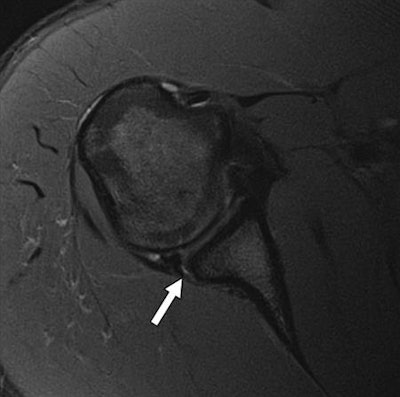

A posterior labral tear (arrow) in a 20-year-old man detected with axial T2-weighted multiplanar 2D fast spin-echo unenhanced standard MRI (above) and the fast five-minute protocol (below) using 3-tesla MRI. Images courtesy of AJR.The key component to reducing imaging time and maintaining diagnostic image quality is having a scanner that can perform parallel imaging. The technology shortens exam time by obtaining a signal from a reduced field-of-view with fewer phase-encoding steps, which allows "images to be acquired with the same resolution as that obtained with a standard sequence in less time," the authors wrote.